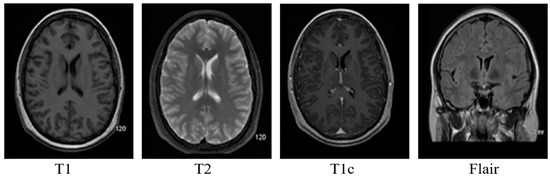

Brain MRI tumors have complicated structures and shapes, which makes the tumor classification and segmentation process more difficult using uni-modality. MRI machines provide an option to capture multimodality images with a more detailed representation of brain tissues [9]. During the MRI scan of a patient, the MRI machine produces different types of MRI sequences including T1, T2, T1c, and Flair, which are based on the Time to Echo (TE), Repetition Time (TR), brightness and contrast values. Figure 3 describes the four different brain MRI modalities and Figure 4 describes the three different types of healthy tissues inside the brain.

Brain MRI provides the option to obtain different image modalities by changing the strength of the magnetic field and timing. Echo time in MR imaging is the time for which the radio frequencies emitted by the excited hydrogen atoms are measured. Repetition time is the time delay between two consecutive echo times. Changing the echo time and repetition time can have four different image modalities.

• T1: This modality has a small echo and repetition time. T1 provides a nice image contrast for the various healthy tissues inside the brain, i.e., gray matter, cerebrospinal fluid and white matter, etc.

• T2: It has a long time of echo and repetition time but slow image acquisition. It provides good contrast for the tumor surrounding tissues (edema).

• T1c: It is the same as T1, but a contrast agent is applied to enhance the contrast.

• FLAIR: It is used to nullify the signal from the fluid, suppress the effect of Cerebrospinal Fluid (CSF), and bring out the periventricular hyperintense lesion.

Figure 3. Pictorial view of brain MR Image modalities.